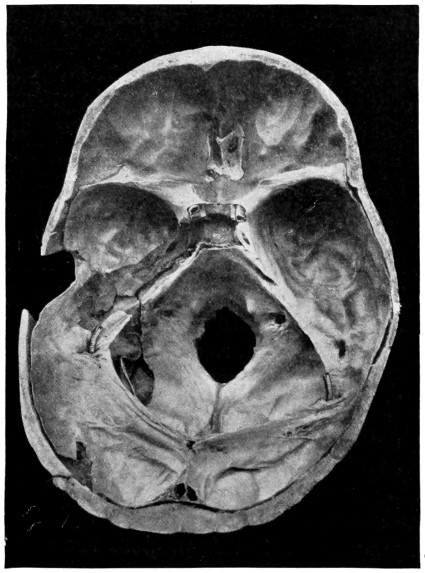

| 29 A and B. The base of the skull and the base as seen on transillumination | 70, 71 |

| 50 A and B. The inner aspect of the skull and the same seen on transillumination | 137 |